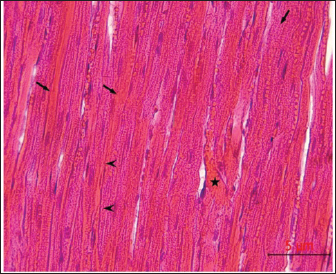

Post-mortem examination resultsPost-mortem examinations of the dead horses infected with M. haemofelis revealed signs of overall emaciation in the affected animals, paleness of internal organs (Fig. 5), and prominent splenomegaly. The liver, kidneys were enlarged; however, the heart showed white patches. Moreover, histopathological changes were characterized by different histopathological changes of eosinophilic degeneration of cardiac muscle fibers, accompanied by atrophy in some fibers, with bleeding between fibers, besides atrophic glomeruli, accompanied with the dilatation of renal tubules in the kidneys, as well as marked reduction in the proportion of white pulp of splenic tissue and degenerative changes in the cytoplasm of hepatocytes, accompanied by nuclear alterations characterized by loss of chromatin content in the hepatic tissue (Figs. 6–9).

Fig. 6. Histopathological examination of the heart revealed eosinophilic degeneration (arrows) of cardiac muscle fibers, accompanied by atrophy in some fibers (arrowhead), with bleeding between fibers (asterisk), H&E, 40x.scale bar=5µm.